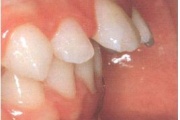

Koonilise kujuga lisahammas ülemiste tsentraalsete lõikehammaste vahel.

Suulaepoolt lõikunud koonilise kujuga lisahammas